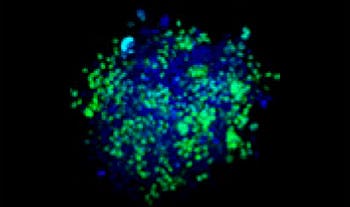

Making the spheroids transparent and imaging them with an FV3000 confocal laser scanning microscope enabled us to image the co-cultured cancer spheroids at depth. Staurosporine treatment increased the number of dead cells in a dose-dependent manner (Fig. 2*1). Three-dimensional analysis is required to determine which cells are dead and how many dead cells there are in a three-dimensional mass.

Figure 2. Drug response in co-culture spheroids

Figure 2. Drug response in co-culture spheroids*1